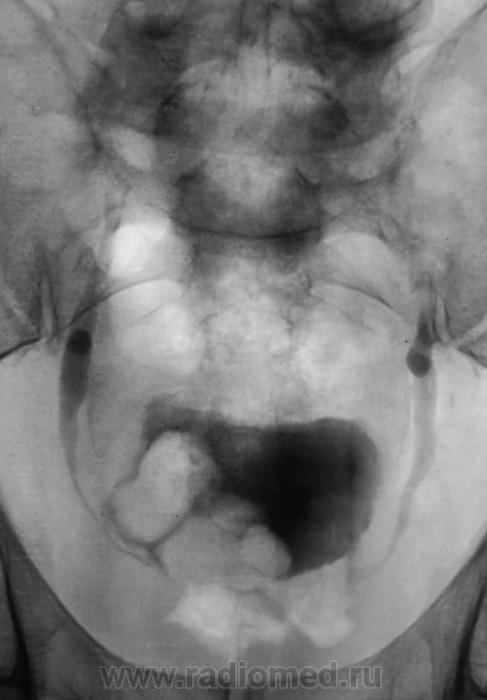

Мочевой пузырь с дефектами наполнения. А что на УЗИ?

Интересно: в мочевом камни или образование?

Пациент, уже в урологическом отделении ОКБ, готовится к операции.